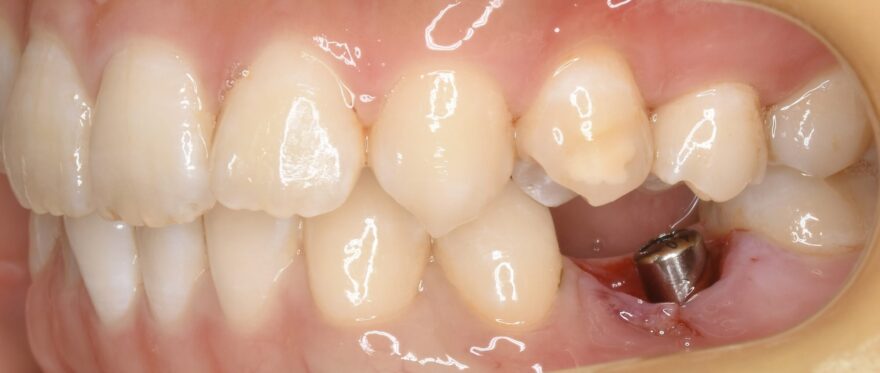

インプラント治療の口腔内写真

ここまでのオペ時間はわずか10分。

もちろん痛みと腫れもありません。